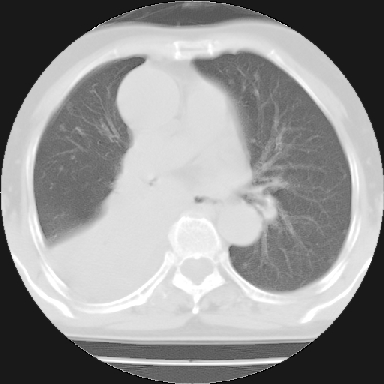

以下是引用苯小孩在2007-4-13 16:20:00的发言:[br]1、右下肺中央型肺癌并阻塞性肺不张、肺内转移、胸椎右侧附件亦有转移<横断层面第8层>.[br]2、右侧胸腔积液.

以下是引用swyyy2007在2007-4-13 15:31:00的发言:[br]右肺门下区肿块,右肺下叶支气管阻塞,右肺下叶不张,右侧大量胸腔积液,右肺中叶见结节状高密度影,边缘清,纵隔内见肿大淋巴结。首先考虑右下肺中心型肺癌伴右肺下叶不张、中叶、纵隔淋巴结转移。右侧胸腔积液。